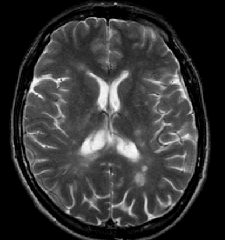

Рассеянный склероз представляет собой аутоиммунную патологию, при которой собственная Далее...

Инсульт — это острое, быстро развивающееся очаговое или диффузное нарушение мозгового Далее...